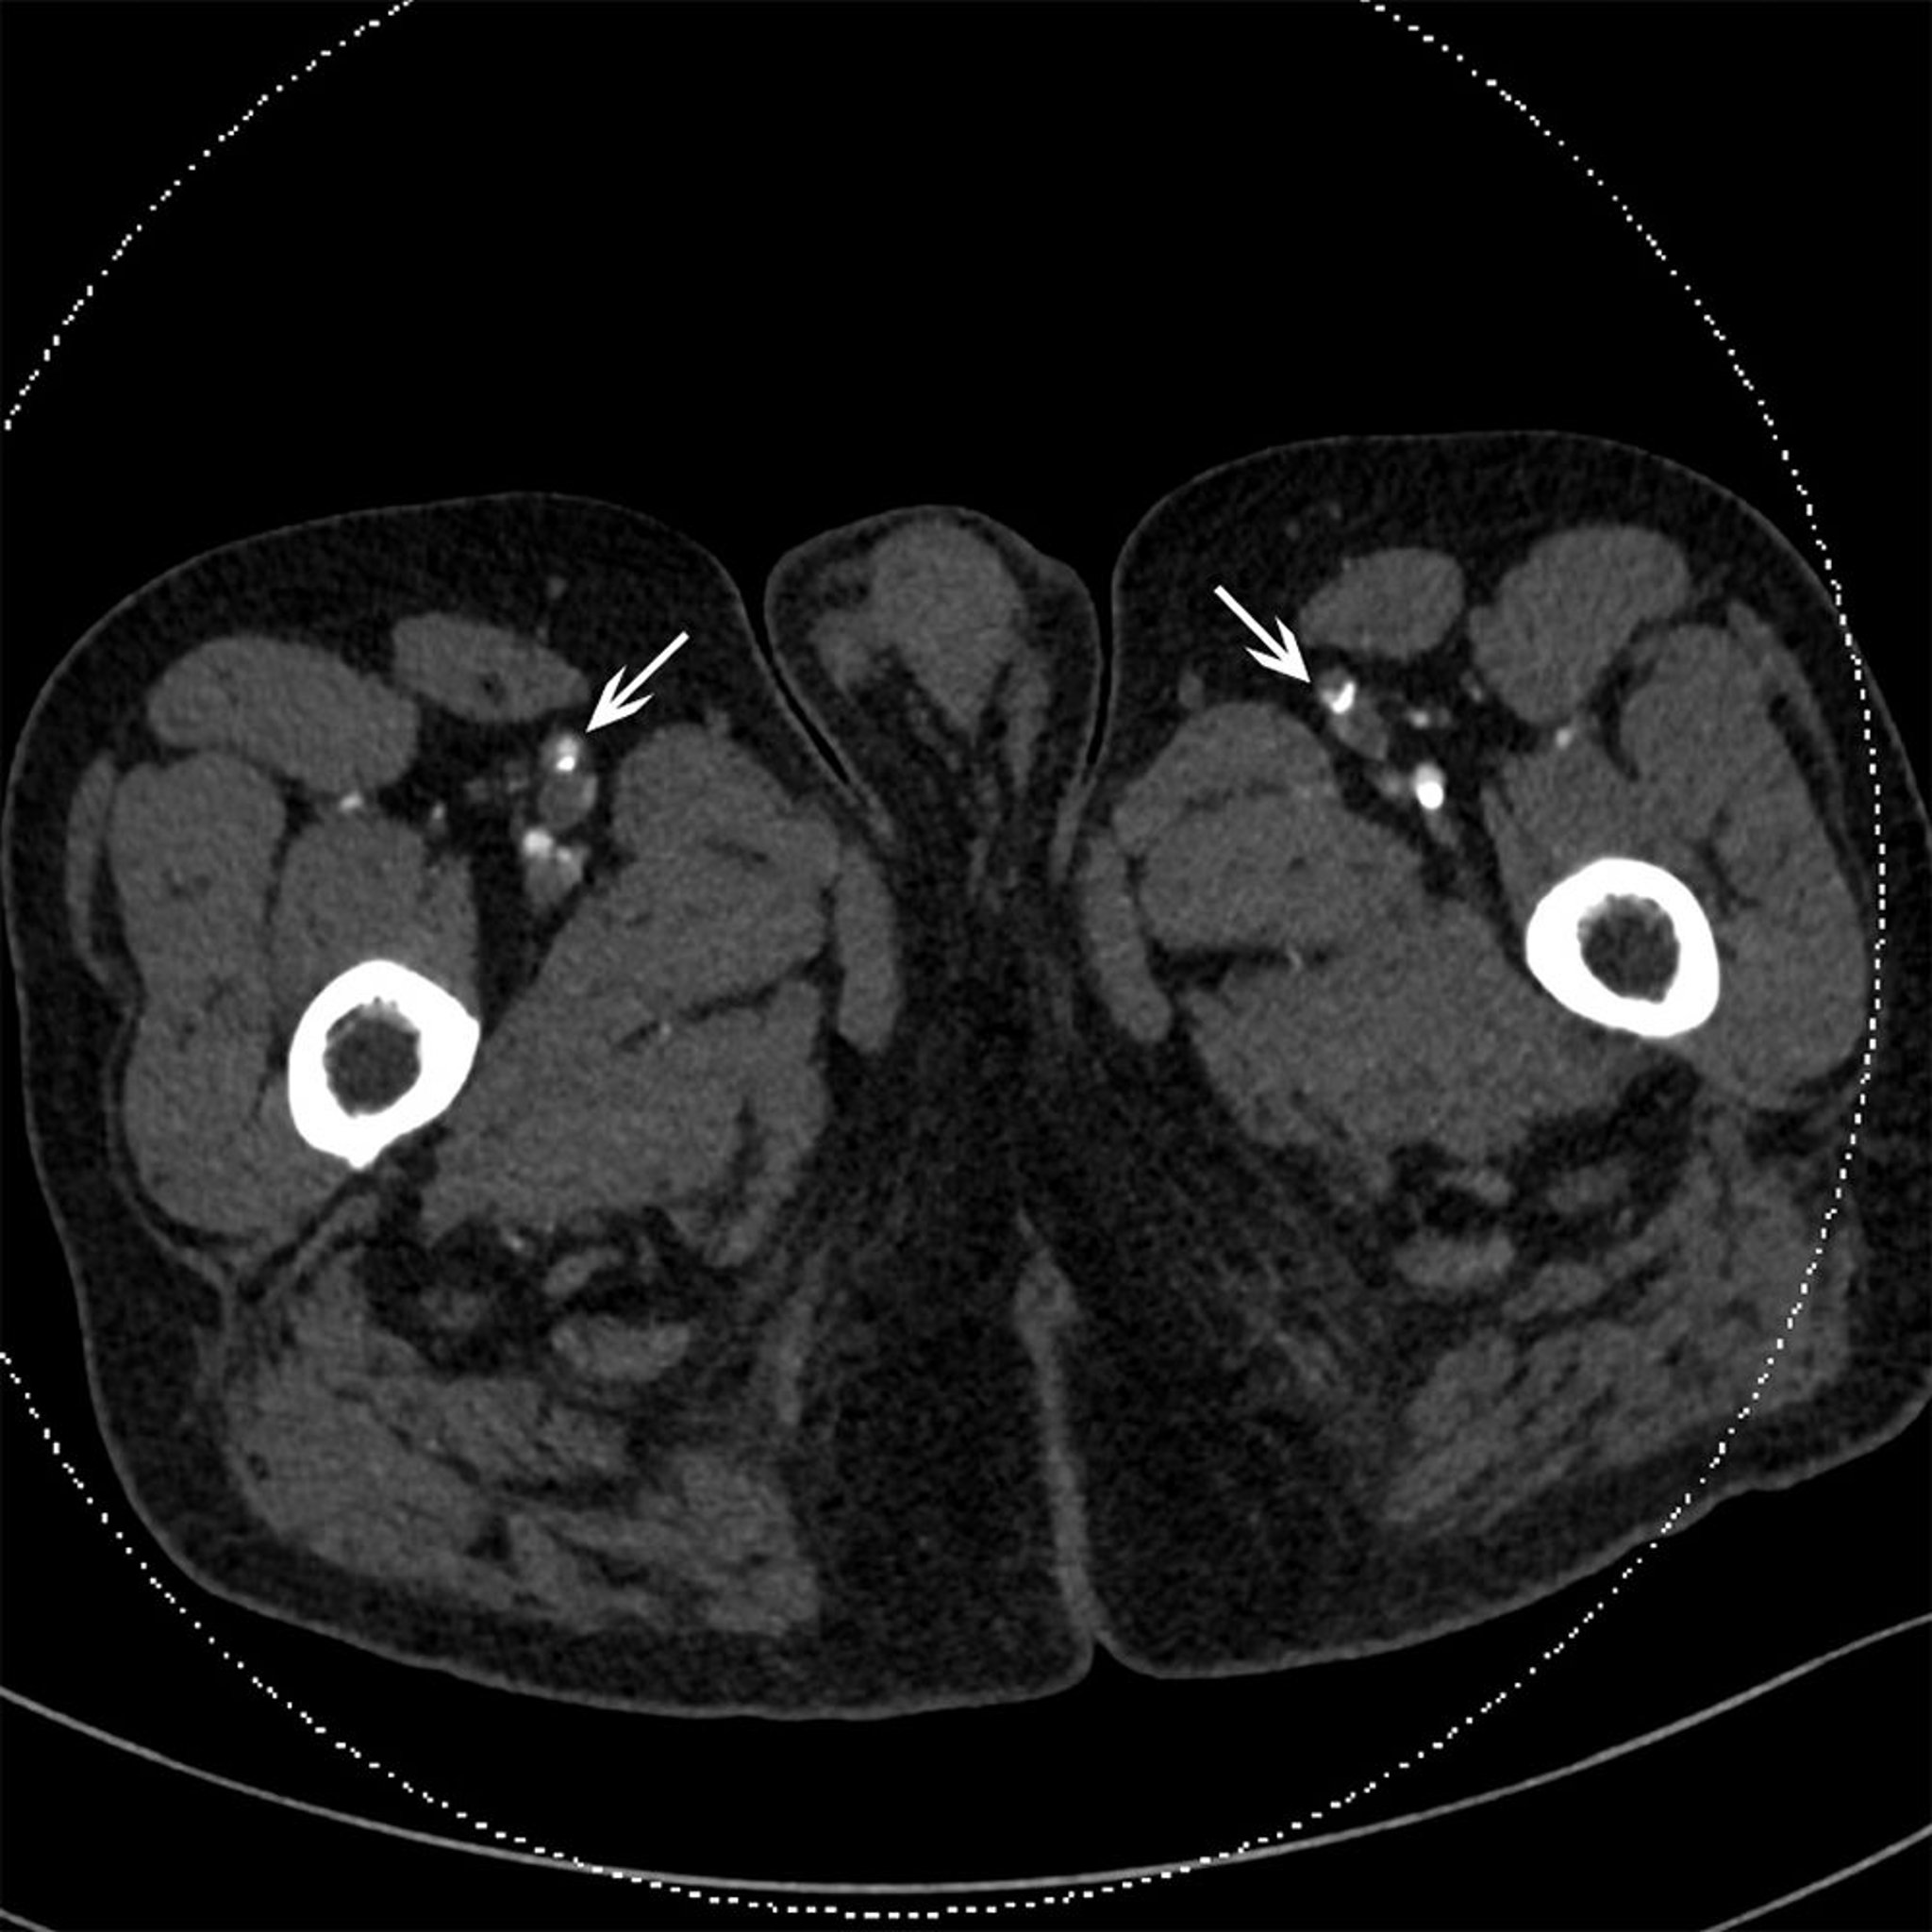

CT Scan of a Patient with Occlusion of Superficial Femoral Arteries

This CT shows bilateral calcified plaque in superficial femoral arteries (arrows).